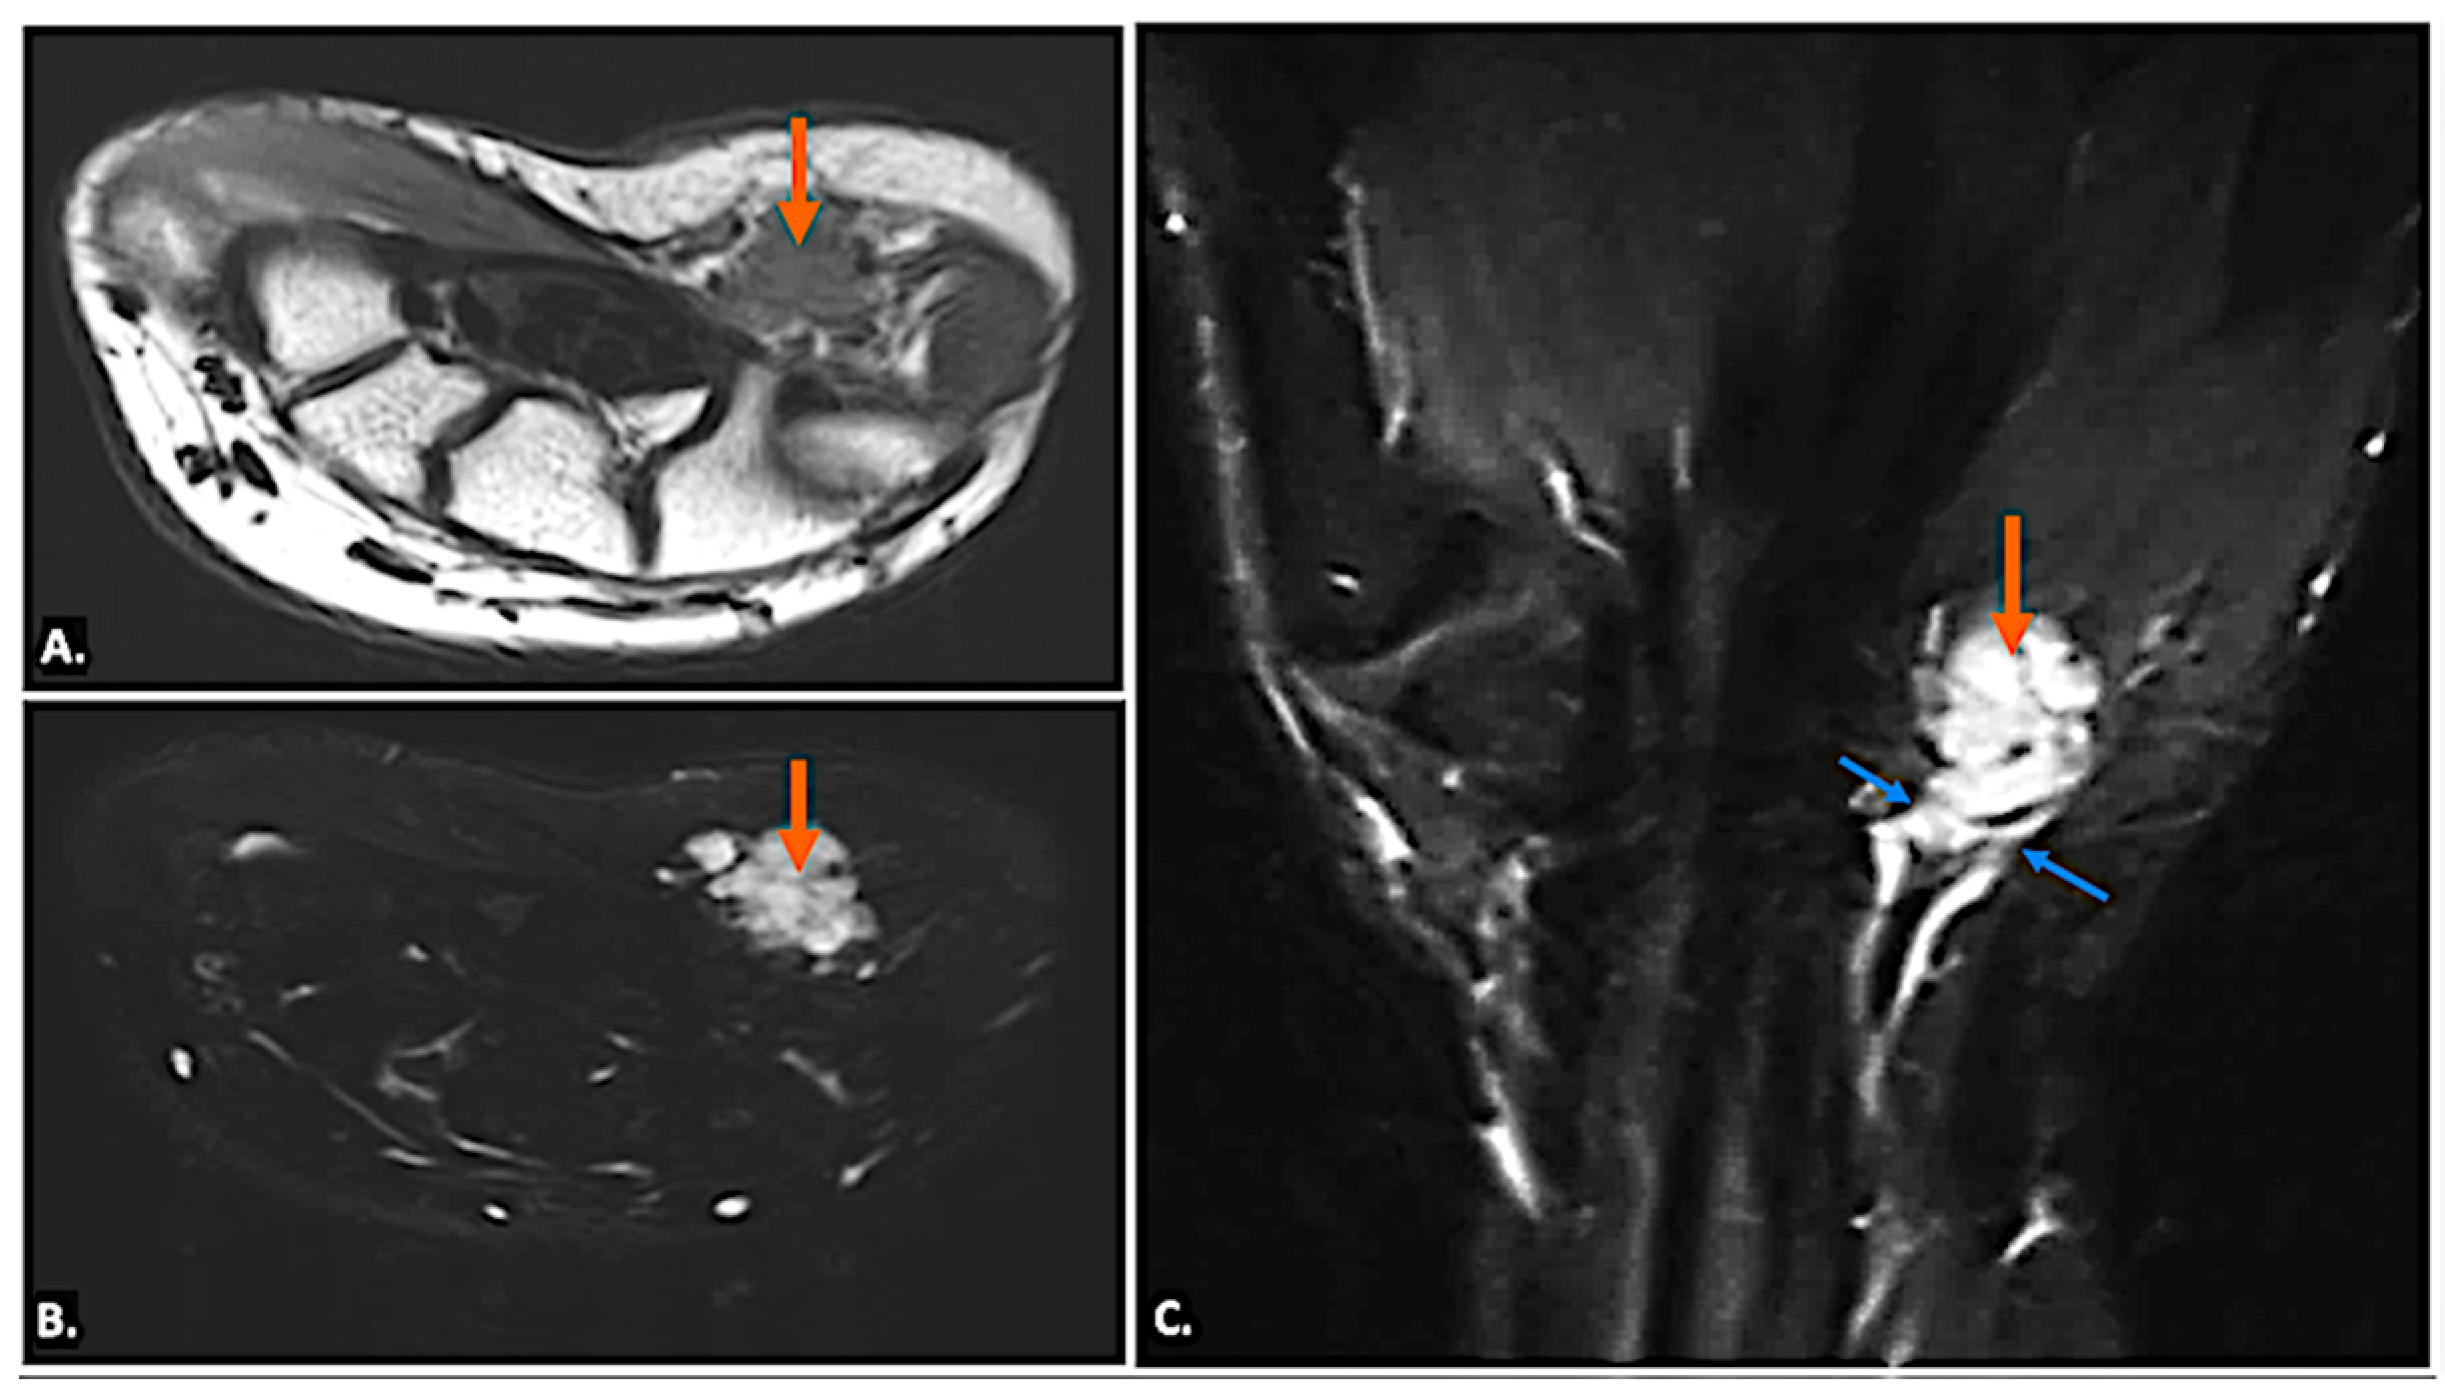

Other pathological conditions affecting Guyon’s canal include vascular abnormalities such as arteriovenous malformation (Figure 15), ulnar artery thrombosis, tortuosity (Figure 16), or aneurysms. Ultrasound imaging will show hypoechoic or anechoic mass with vascular flow seen on Doppler imaging in cases of aneurysm with absence of flow in a case of thrombosis. On MRI, thrombosis is seen as low or high signal intensity within the vessel lumen on both T1- and T2-weighted images, depending on duration. Aneurysms appear as well-circumscribed lesions, potentially with signal voids due to high flow. Pseudoaneurysm will show the presence of adjacent soft-tissue mass in close approximation with the lumen [23].

Figure 15.

(A) T1-weighted axial, (B) T2-weighted, fat-suppressed axial, and (C) T2-weighted, fat-suppressed coronal MR images of an arteriovenous malformation (indicated by the orange arrow) in the region of Guyon’s canal. The lesion appears hypointense on the T1-weighted sequence (A), appears hyperintense on T2-weighted, fat-suppressed sequences, (B) and demonstrates continuity with vessels (blue arrows) (C).

Figure 16.

(A) T2-weighted, fat-suppressed coronal and (B) T2-weighted, fat-suppressed axial MR images reveal the tortuous irregular path of the ulnar artery (orange arrow) in the region of Guyon’s canal, resulting in ulnar neuropathy and causing neuropathic symptoms.